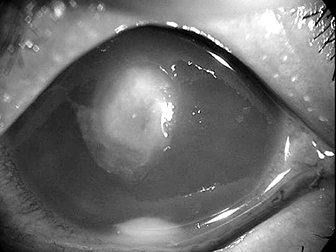

数あるコンタクトレンズ合併症の中で、最も病状が重くなるのはアカントアメーバ感染症です。水道水などを介して侵入し、ケース内で増殖したアカントアメーバがコンタクトレンズを介して角膜に感染を起こしますが、ルーズな装用(時々使用する、あまりレンズケアをしない、指定期間を越えて使用する、水道水で洗浄)をしている人に圧倒的に多く見られます。

アカントアメーバによる角膜感染

先進国においては、コンタクトレンズ装用が細菌性角膜炎の危険因子のトップを占めています。臨床的によく見られるのは、緑膿菌やセラチアなどのグラム陰性桿菌と表皮ブドウ球菌やアクネス菌などのグラム陽性菌です。

実際、レンズケース内の液を培養すると、非常に高い頻度でグラム陰性桿菌が分離されることから、ケースが感染の温床になっていることがうかがわれます。特に緑膿菌は非常に強い病原性を持つため、迅速な対応が必要で、タイミングを誤ると失明してしまうこともあります。

緑膿菌による角膜感染